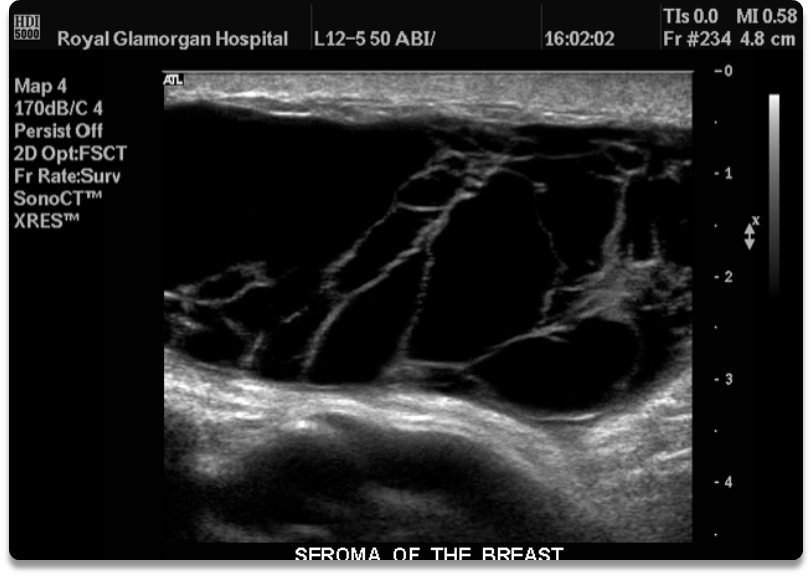

What is this image showing?

seroma